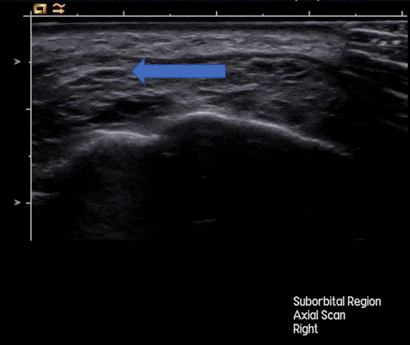

После курса плазмотерапии УЗ-картина гранулем существенно изменилась (рис. 3): наблюдалось статистически значимое (p < 0,001) уменьшение линейных размеров и объема образований.

Рис. 3. Ультразвуковая картина регресса гранулемы инфраорбитальной области после проведения курса аутологичной плазмотерапии (через 1 месяц).

Составлено авторами по результатам данного исследования

Наблюдается уменьшение размеров, доли гипоэхогенного компонента. Образование стало более однородным, эхогенность его в целом повысилась, контур стал четким, ровным, гиперэхогенным - признаки замещения воспалительного инфильтрата фиброзной тканью. Средний размер гранулемы сократился до 2,5 ± 1,8 мм (уменьшение на 70,2%). В 72% случаев гранулемы полностью регрессировали, а на контрольном УЗИ определялись лишь минимальные изменения структуры и эхогенности тканей (в виде локальных неоднородно гиперэхогенных участков) без признаков наличия цветовых картограмм потоков внутри и непосредственно перифокально, которые могли трактоваться как соответствующие фиброзным изменениям. В оставшихся случаях образований отмечалось повышение эхогенности внутреннего содержимого, четкости, ровности и эхогенности контуров и полное исчезновение признаков наличия цветовых картограмм потоков при ЦДК, что могло отражать трансформацию активной гранулемы в стадию фиброза и ремоделирования.